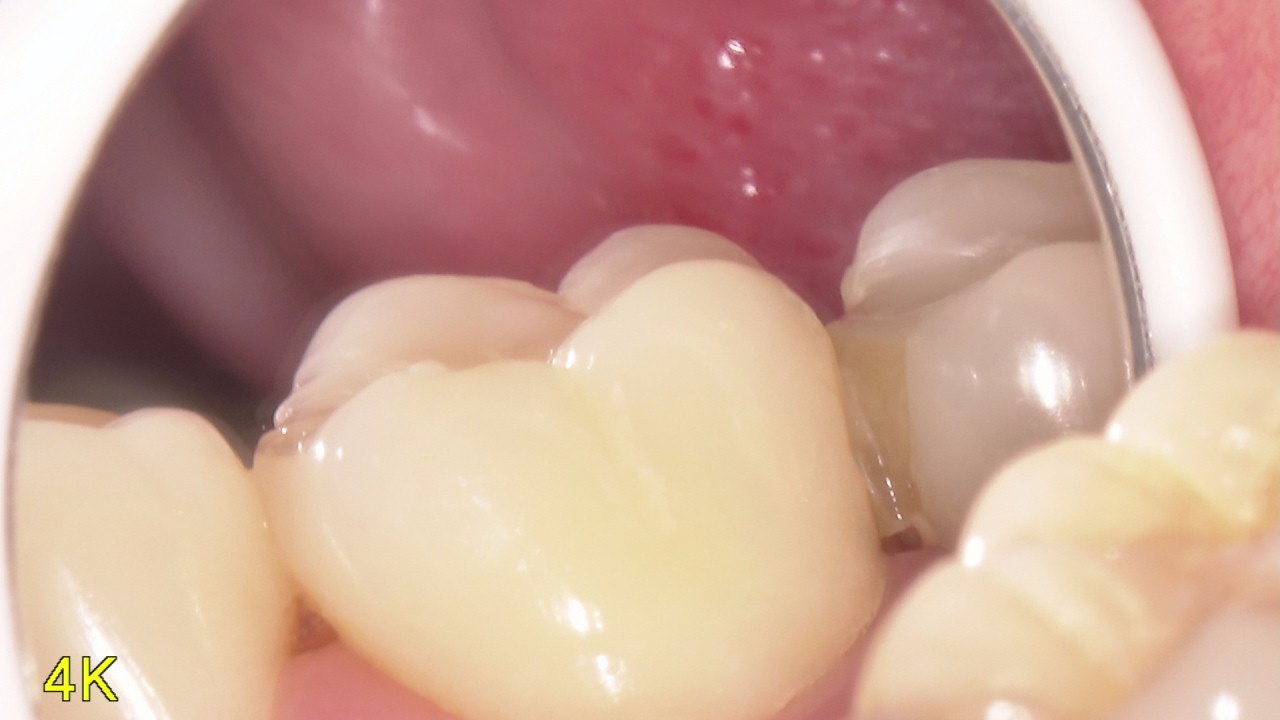

写真を用いたセラミック治療の解説

こんにちは今日はセラミック治療ってどんなものか写真を使いながら説明していこうかなと思っています。 まずこの写真みてもらってもいいですか? 左上7番目と6番目の間にCRというプラスチックの樹脂がうめこまれています。歯の形を […]